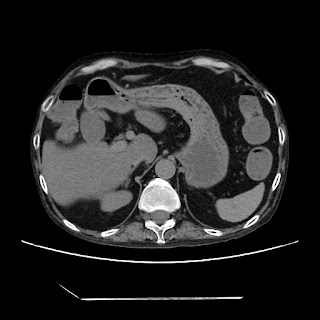

HRCT done on 17Mar16